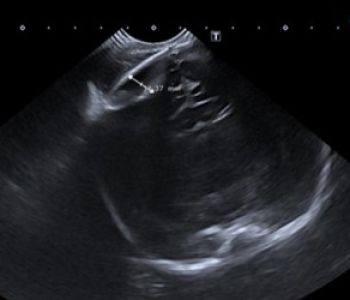

Recién nacido de 35+3 semanas, segundo gemelo de una gestación bicorial-biamniótica que desarrolla en el período fetal un cuadro de crecimiento intrauterino retardado y prenatalmente se detecta una comunicación interventricular, una arteria subclavia derecha aberrante, una arteria umbilical única y una agenesia de ductus venoso.